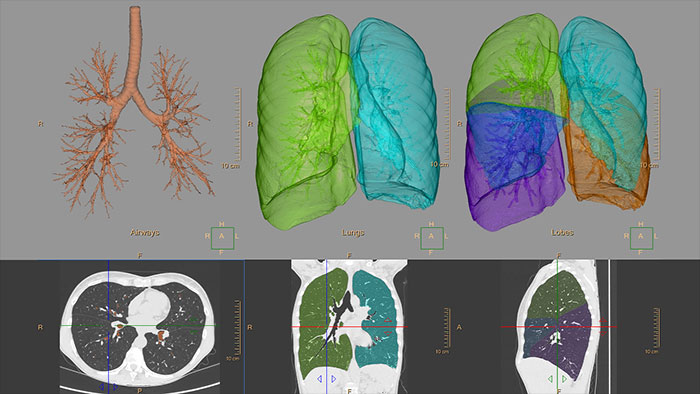

The clinical application helps visualize and quantify the destructive process of diffuse lung disease (e.g. emphysema), providing a guided workflow for airway analysis, reviewing and measuring airway lumen, and assessing air trapped.

CT COPD helps visualize and quantify the destructive process of diffuse lung disease (e.g. emphysema). The application provides a guided workflow for airway analysis, reviewing and measuring airway lumen, and assessing air trapped.